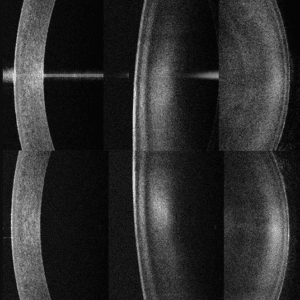

Topógrafo Corneal Huvitz HTG-1

Biómetro Óptico HBM-1

Modulo de biometría